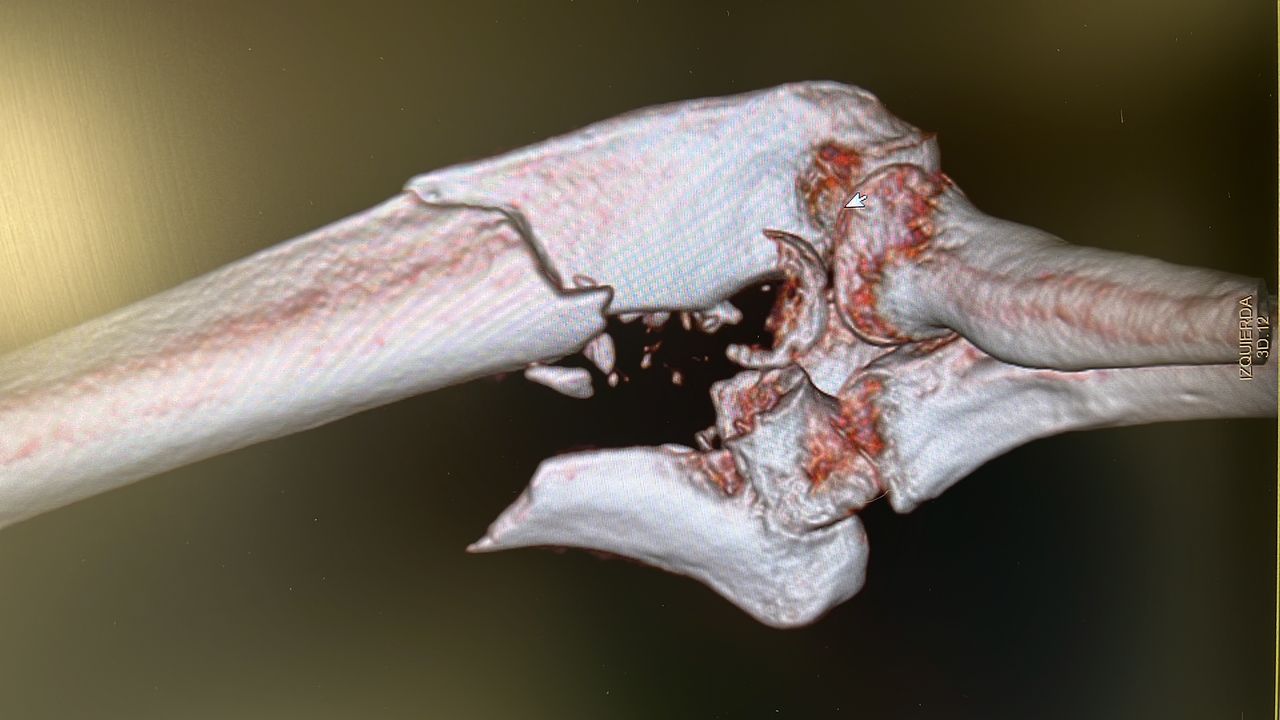

Fotos y vídeos